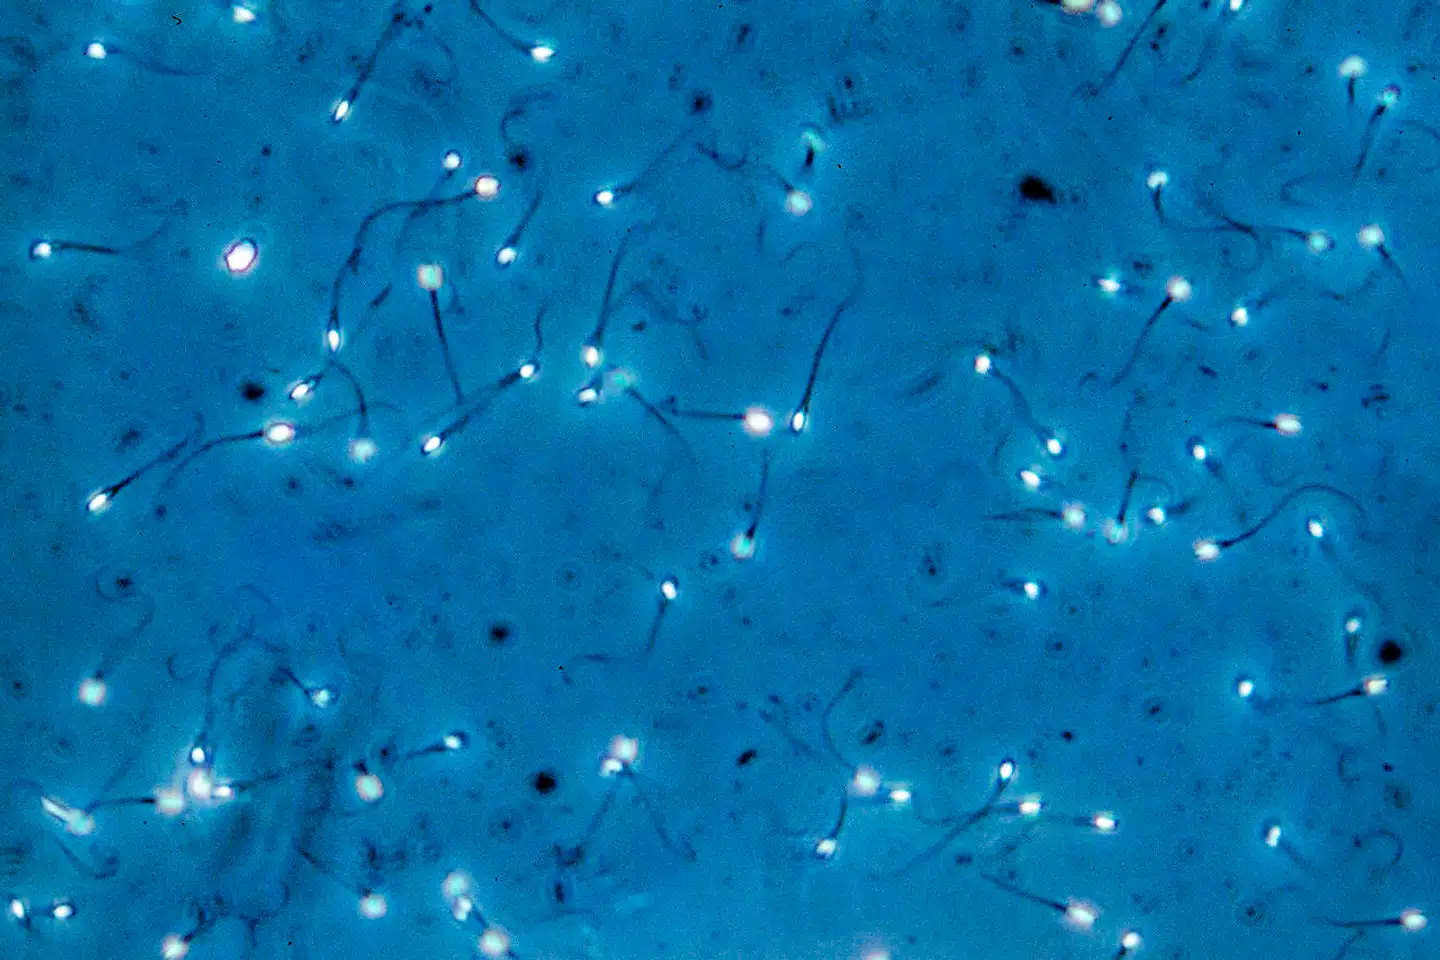

De mange danske mænd med dårlig sædkvalitet skal skynde sig at få børn. Det viser ny forskning fra Rigshospitalet.

Det er første gang, at forskerne har påvist, at sædkvaliteten falder drastisk, som tiden går, hos mænd med i forvejen ringe sædkvalitet.

»Vi mente tidligere, at sæden havde den kvalitet, den nu engang havde. Men det ser ud til, at den kun bliver dårligere med tiden, så de til sidst ikke kan få børn længere,« siger lederen af studiet, overlæge Niels Jørgensen fra Klinik for Vækst og Reproduktion på Rigshospitalet.

»15 procent af de unge mænd har så dårlig sæd, at de ikke kan bliver fædre uden fertilitetsbehandling. Men i alt har 40 procent af de danske mænd så dårlig sæd, at det påvirker deres chancer negativt for at blive far i større eller mindre grad,« siger han.

»Hvis du har ekstremt dårlig sædkvalitet, er der stor risiko for, at det hurtigt bliver værre. Så du bør gå i gang med fertilitetsbehandling hurtigst muligt, hvis du ønsker børn,« siger Niels Jørgensen.

Forskerne har gennem 15 år fulgt 137 yngre, raske mænd, fra de var 33 år og til 48 år.